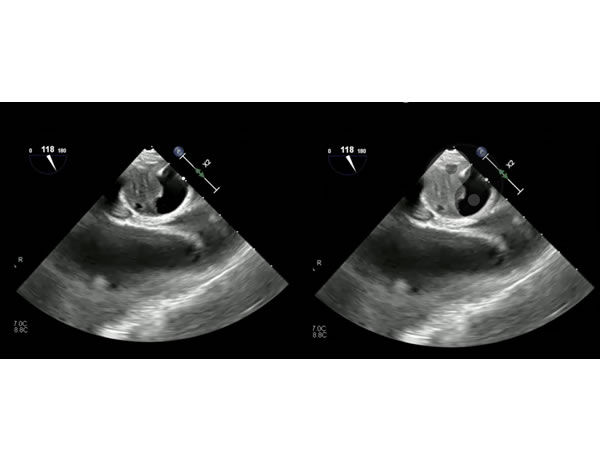

Válvula aórtica tetravalva en una paciente con comunicación inter auricular y ductus arterioso persistente